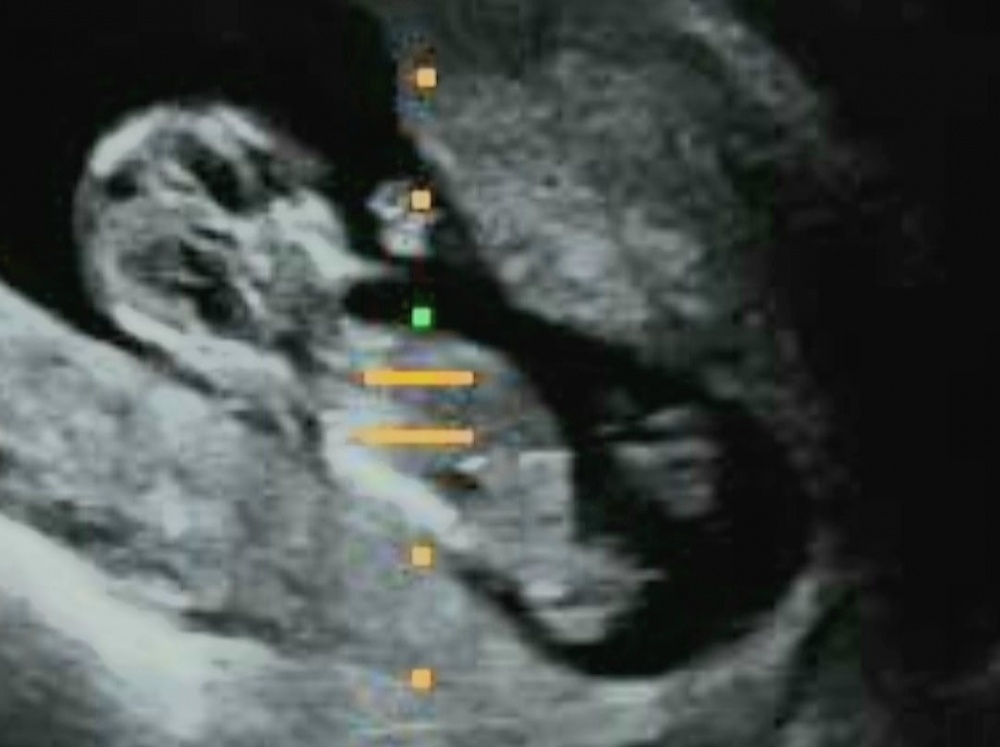

Hallo Zusammen:)

was denkt ihr hier?

links po und rechts in der mitte das Geschlechtsteil:)